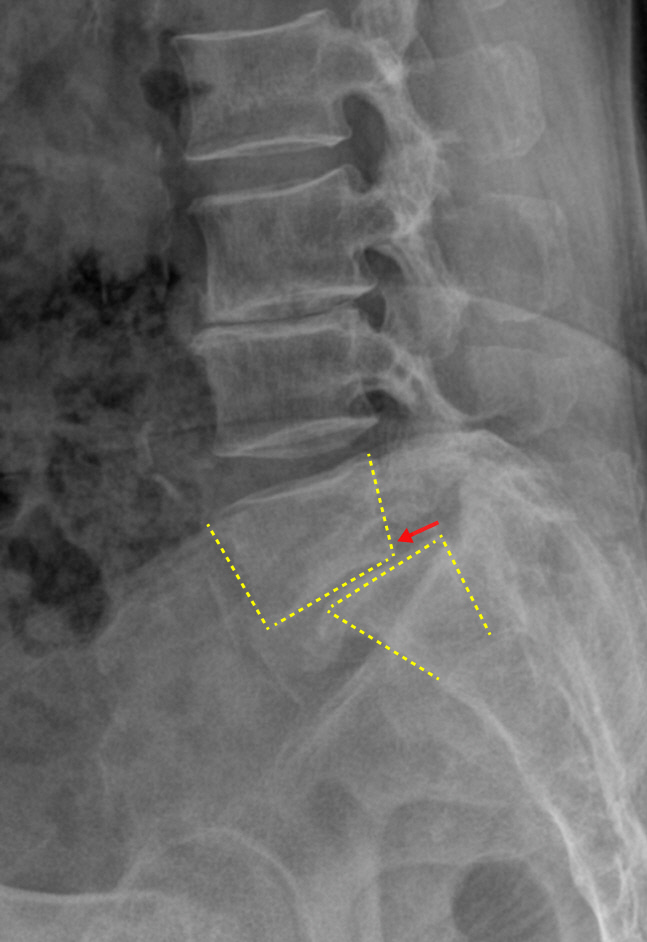

통증의 정확한 원인을 찾기 위해 우선 엑스레이 촬영을 했다. 엑스레이 사진을 보니 허리 척추뼈가 앞으로 밀려나있는 전방전위증을 보였다. 또한 허리를 굽혔다 펼 때 척추의 배열이 과하게 움직이는 불안정성도 관찰되었다. 척추전방전위증과 척추 불안정성이 함께 있으니 허리를 굽혔다 펼 때마다 통증이 심할 수밖에 없었다.

척추전방전위증은 척추뼈 사이의 관절과 디스크가 불안정해져서 척추뼈가 정상 위치보다 앞 혹은 뒤쪽으로 이동해 허리통증과 다리저림을 일으키는 질환이다. 어긋난 척추뼈 자체의 구조적 문제로 척추신경이 지나가는 신경구멍이 좁아져 증상이 유발된다.

진단은 다양한 자세에서 엑스레이를 촬영해 척추의 변화를 관찰하는 것이 기본이다. 여기에 MRI와 CT를 이용하여 척추신경, 뼈 그리고 척추관절의 상태를 평가하는 것이 가장 중요하다. 이러한 종합적인 검사를 통해 정확한 진단을 한 후 환자 상태와 증상에 따라 치료 방법을 결정하게 된다.